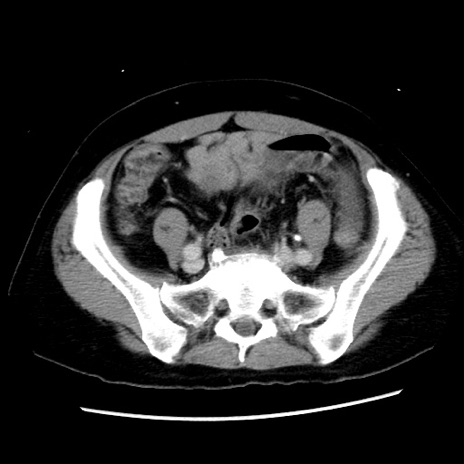

冠状断像

【症例】 50歳代女性

【主訴】 腹痛

【現病歴】前日生レバーを食べた。今朝に排便あり。 昼前に突然発症の腹痛を生じ、当院救急外来を受診した。

【既往歴】 子宮筋腫にてで子宮全摘後

【身体所見】 意識清明、腹部:平坦、軟、下腹部やや左を中心に圧痛・反跳痛あり、筋性防御あり

【データ】WBC 7800、CRP 0.07